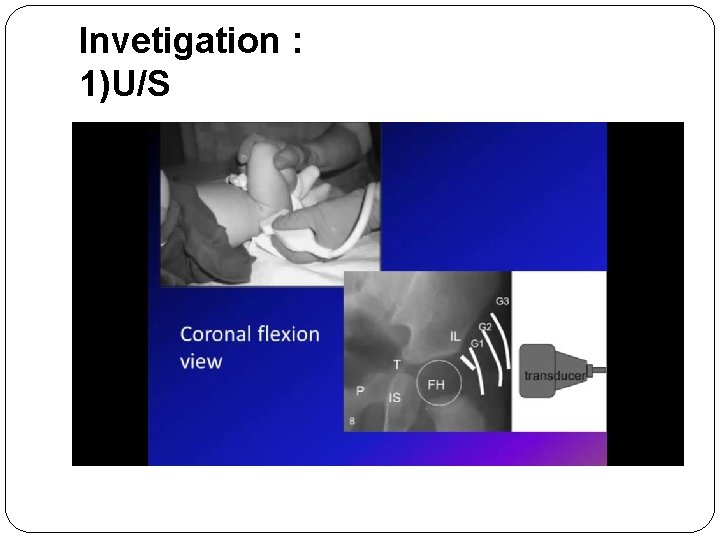

Invetigation : 1)U/S